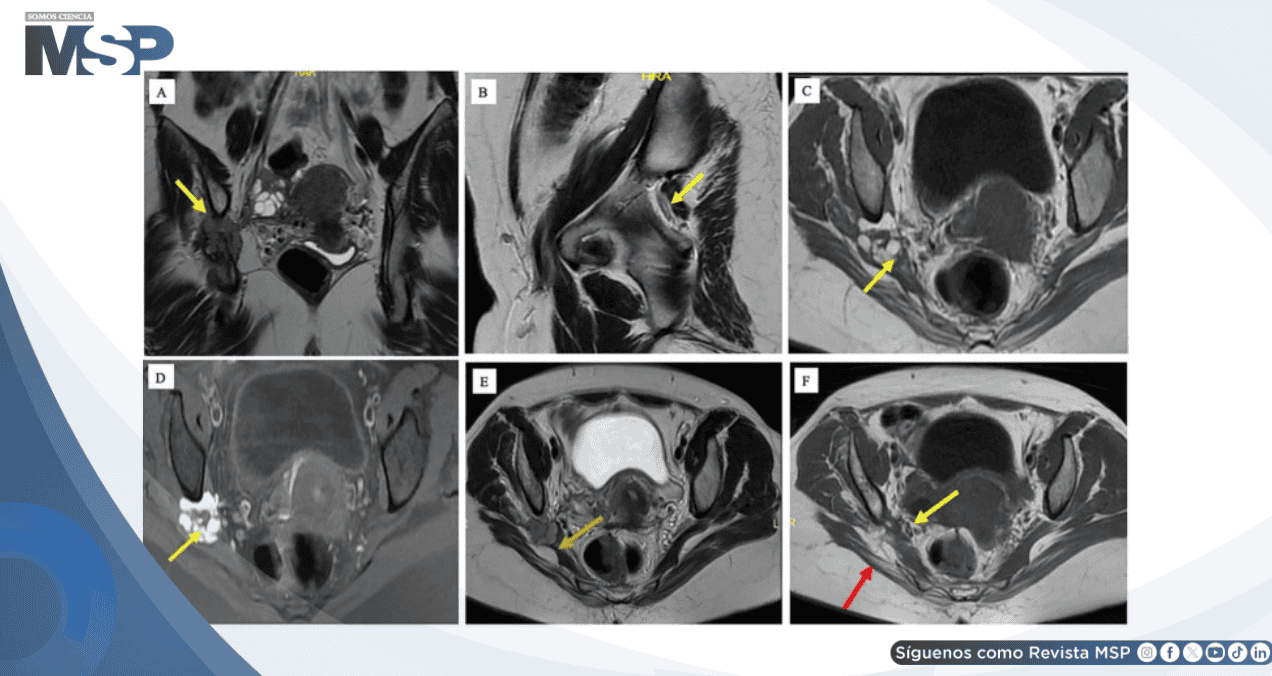

En la presentación actual, la ecografía transvaginal evidenció endometriosis infiltrante profunda pélvica. La resonancia magnética pélvica reveló una lesión endometriósica de 4 cm comprometiendo el nervio ciático derecho adyacente al foramen ciático mayor.

La masa medía 32 × 16 × 30 mm con múltiples quistes coalescentes mostrando patrón de señal hemático característico. El nervio ciático se encontraba completamente obliterado con afectación de 5.2 cm de longitud. Se documentó atrofia muscular de piriforme y glúteos, evidenciando daño crónico.

Este caso ilustra la importancia del reconocimiento del patrón de "ciática catamenial" que, a pesar de ser comunicado explícitamente por la paciente, no fue identificado inicialmente. La resonancia magnética demostró ser esencial con sensibilidad del 90% y especificidad del 98%. La presencia de atrofia muscular evidenció la severidad del daño neurológico resultado del retraso diagnóstico.